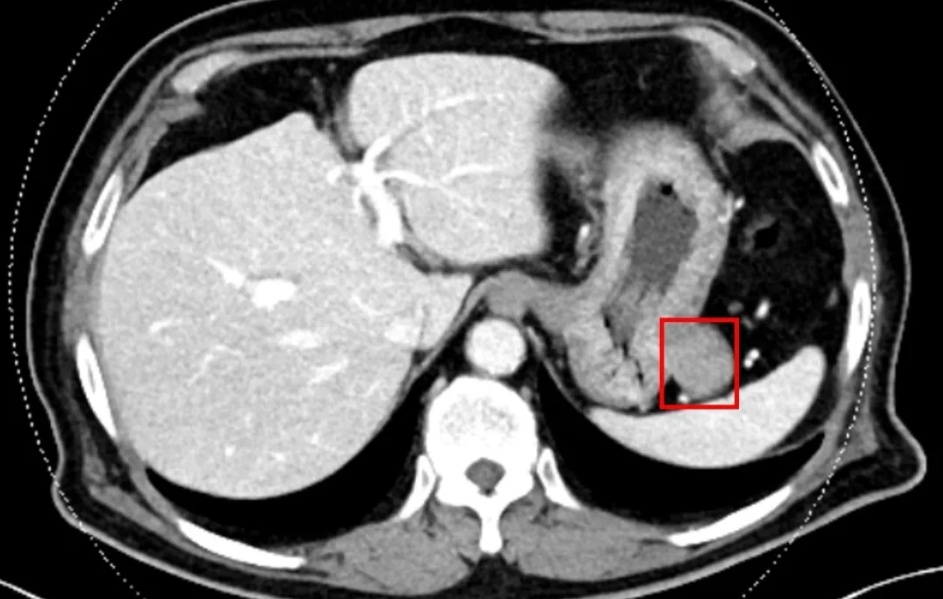

34岁女子体内深埋16颗肿瘤,如何精准手术“一键清除”?

婷婷(化名)今年刚刚34岁,她从小就患上了乙肝,长期服用抗病毒药,没想到,2024年7月乙肝随访检查时,她又被告知罹患“肝脏肿瘤”。随后的肠镜报告显示乙状结肠腺癌,就是它导致了婷婷的肝脏出现了多发转移病灶。